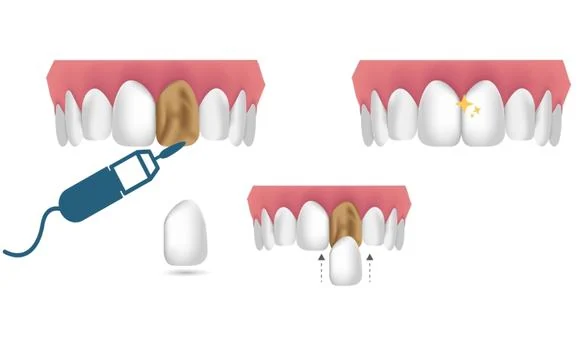

2. Porcelain Veneers: Porcelain veneers are thin shells custom-made from high-quality dental porcelain. They are bonded to the front surface of the teeth, creating a natural-looking and long-lasting smile transformation. Porcelain veneers are highly resistant to stains and offer superior aesthetics.

The specific procedures involved in a Hollywood Smile vary depending on the individual treatment plan. Generally, the operation may include teeth whitening to achieve a bright base color, dental contouring to reshape and align the teeth, and the placement of veneers or other dental restorations. The dentist will ensure patient comfort throughout the process, and local anesthesia may be administered if necessary.